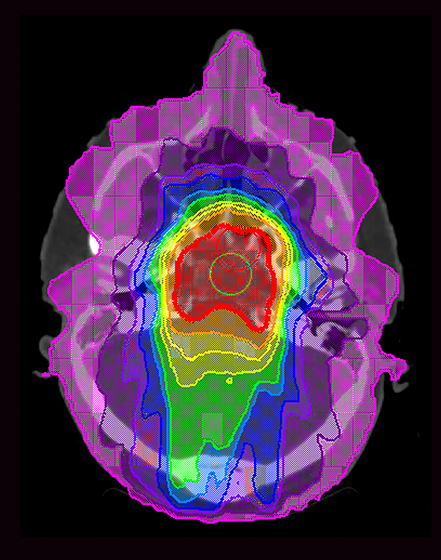

The researchers compared the prevalence of cancer in normal mice to those with a mutation in the Nf1 gene, which encodes a tumor-suppressing protein called neurofibromin. Children born with mutations in this gene have neurofibromatosis 1, a condition that predisposes them to tumors. In order to parallel the effects of radiation therapy on pediatric patients, young mice underwent focused radiation targeted to the abdominal wall. The dosing was similar to that received by patients.